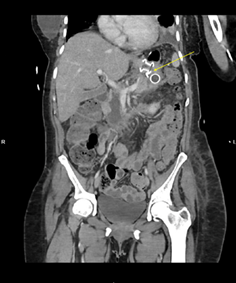

Five days later, a follow-up

CT scan of the abdomen and pelvis revealed extensive pancreatic and

peripancreatic necrosis extending bilaterally to the pelvis, with some

improvement in the previously noted walled-off necrosis in the body and neck,

where a pigtail catheter was already in place. After careful consideration by a

multidisciplinary team, it was decided to proceed with an EDGE procedure,

involving the placement of a lumen-apposing metal stent (LAMS) at a

cysto-gastrostomy through a gastro-gastric (GG) fistula at the remnant stomach,

to drain necrotic pancreatic and peripancreatic material (Figure 4). Two

Figure 4: CT image with necrotizing

pancreatitis and lumen-apposing metal stent (LAMS) at a cysto-gastrostomy

(Yellow arrow)